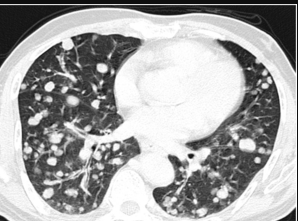

Paciente de 60 años de edad con una masa en colon de 6 meses de evolución. La paciente presenta hematoquecia y perdida de peso.

Se realizó una biopsia de la neoplasia y se observan  los siguientes hallazgos microscópicos.

También se realizaron estudios de imagen a nivel de la cavidad torácica y abdominal y se observaron múltiples lesiones hepáticas y pulmonares intraparenquimatosas.

Del siguiente caso podemos afirmar lo siguiente excepto.